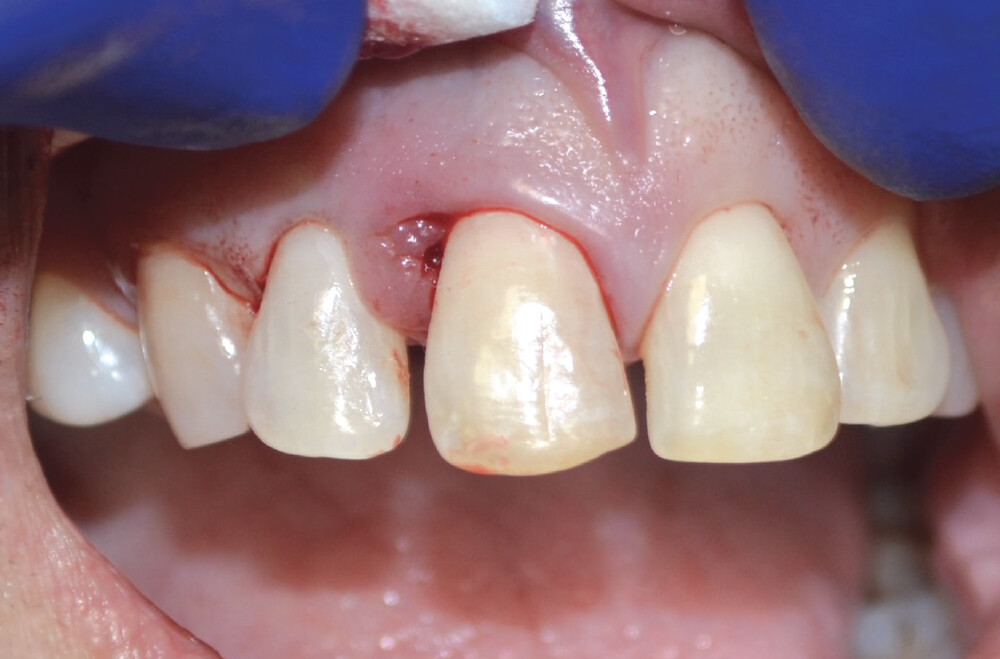

A temporary appliance was delivered and the site allowed to heal. After approximately three months, the healing abutment was removed and stability was checked with a Penguin RFA® A small amount of gingival recontouring was completed with a diode laser, and impressions were taken. The final BruxZir® Esthetic restoration was delivered, and final adjustments were made.